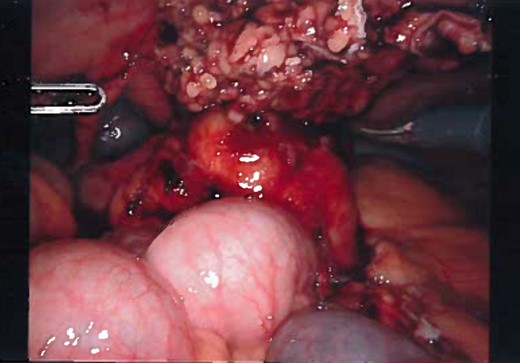

Patient was administered general anesthesia with placement of endotracheal tube. She was placed in lithotomy position (stirrups), both arms tucked at sides, strap secure across chest and a bair hugger (warmer) was placed around upper chest/head/neck area. Our patient was prepped with betadine for a vaginal/perineal prep and chloroprep was used on the abdomen. After sterile draping of the patient, and official time-out with all in agreeance, the Urologist evaluated the bladder with a cystoscopy using a 70° scope to survey for any persistent urachal abnormalities, and confirmed that no fistula/congenital abnormalities from inside bladder. General Surgeon scrubbed in and proceeded with insertion of veress needle and insufflated the abdominal cavity with CO2. Once the abdominal pressure reached 15 mmHg, General Surgeon used a 5 mm/0° laparoscope inside a 5 mm first-entry trocar and watched himself insert the trocar through each layer until passing through the peritoneum and into the abdominal cavity. Two 8 mm robotic Xi trocars were inserted, a 12 mm AirSeal Assistant port, and the 5 mm first entry port was replaced with a third robotic 8 mm cannula. Altogether 3–8 mm robotic ports, a 12 mm assistant port, and a 30° robotic scope was utilized during the case. Docking of the robot followed port placement with ‘renal right’ selected on the patient cart while the patient was placed in slight Trendelenburg. Da Vinci Xi instruments used were a fenestrated bipolar and a monopolar scissor to begin dissection. Initial survey of abdomen confirmed that there is an extension of a structure from the dome of the bladder to the posterior surface of the umbilicus (Fig. 4) and more suggestive of an infected urachal cyst. Further evaluations revealed that the cyst surrounding the umbilicus is inflamed and had multiple pus filled cavities. A complete resection of the cyst and the connecting structure was resected by Da Vinci Xi robotic system (Fig. 5). The bladder was filled with 300 ml of sterile normal saline mixed with methylene blue dye through the Foley catheter to determine any bladder otomies from the dissection. None were present. Urologist over sewed a thin area of the bladder with a 3-0 vicryl SH suture (Fig. 6). Complete resection of the cyst was performed successfully (Fig. 8). Slight irrigation was used to check for bleeding and the specimen was put in an endocatch bag to be retrieved when ports are ready for removal. A 19 Fr Blake drain was placed in the abdominal cavity and secured with a 2-0 nylon suture. Foley catheter is also indwelling.

Inflamed and necrotic appearance of the urachal cyst with multiple pus filled cavities.

Laparoscopic view of the urachal cyst, viewing the umbilical portion of the urachus.